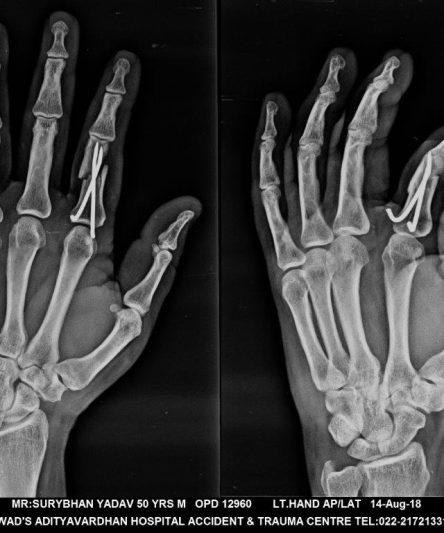

Microskan with Ultra high frequency can take the Lateral Lumbar Spine image of a 90 kg Patient with the correct image receptor